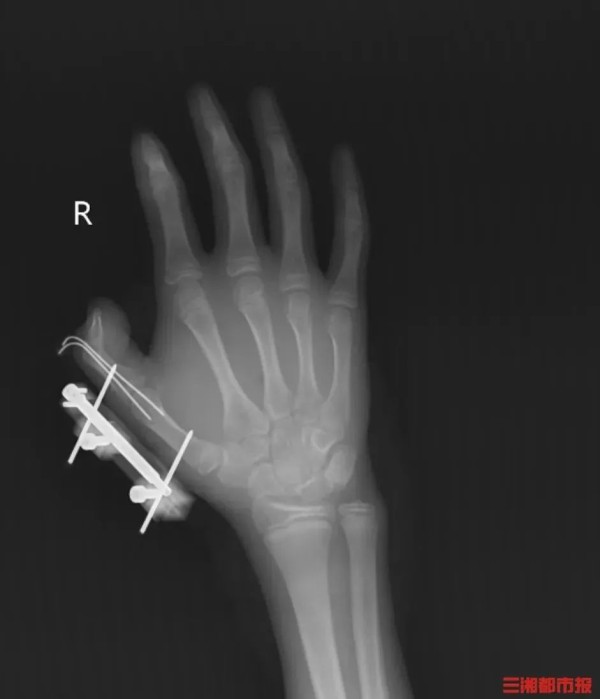

14岁少年手指被炸得深可见骨

前不久,湖南一名14岁的少年维维(化名),在爸爸网购冰淇淋的箱子里发现了用于冷藏的干冰,便拿走当成玩具玩,捏在手里反复摇晃。

突然,密封袋里的干冰发生爆炸,维维的右手瞬间鲜血直流,拇指虎口处被撕开一道约10厘米的伤口,深可见骨,肌肉组织断裂外露,还伴随着拇指骨折、关节脱位,整个拇指完全失去知觉。

见状,家人赶紧带他到当地医院包扎,随后紧急转往湖南省人民医院手足显微外科。经治疗,维维的拇指保住了,但后续还需长期康复训练,才能慢慢恢复手部精细动作功能。